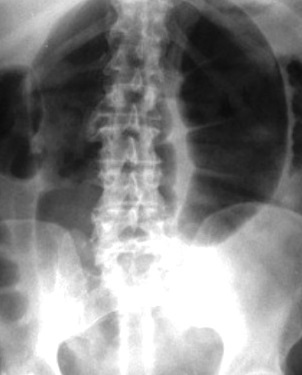

Quais os achados radiográficos que sugerem obstrução intestinal em Cólon?

Distensões periféricas e formação de haustrações visíveis